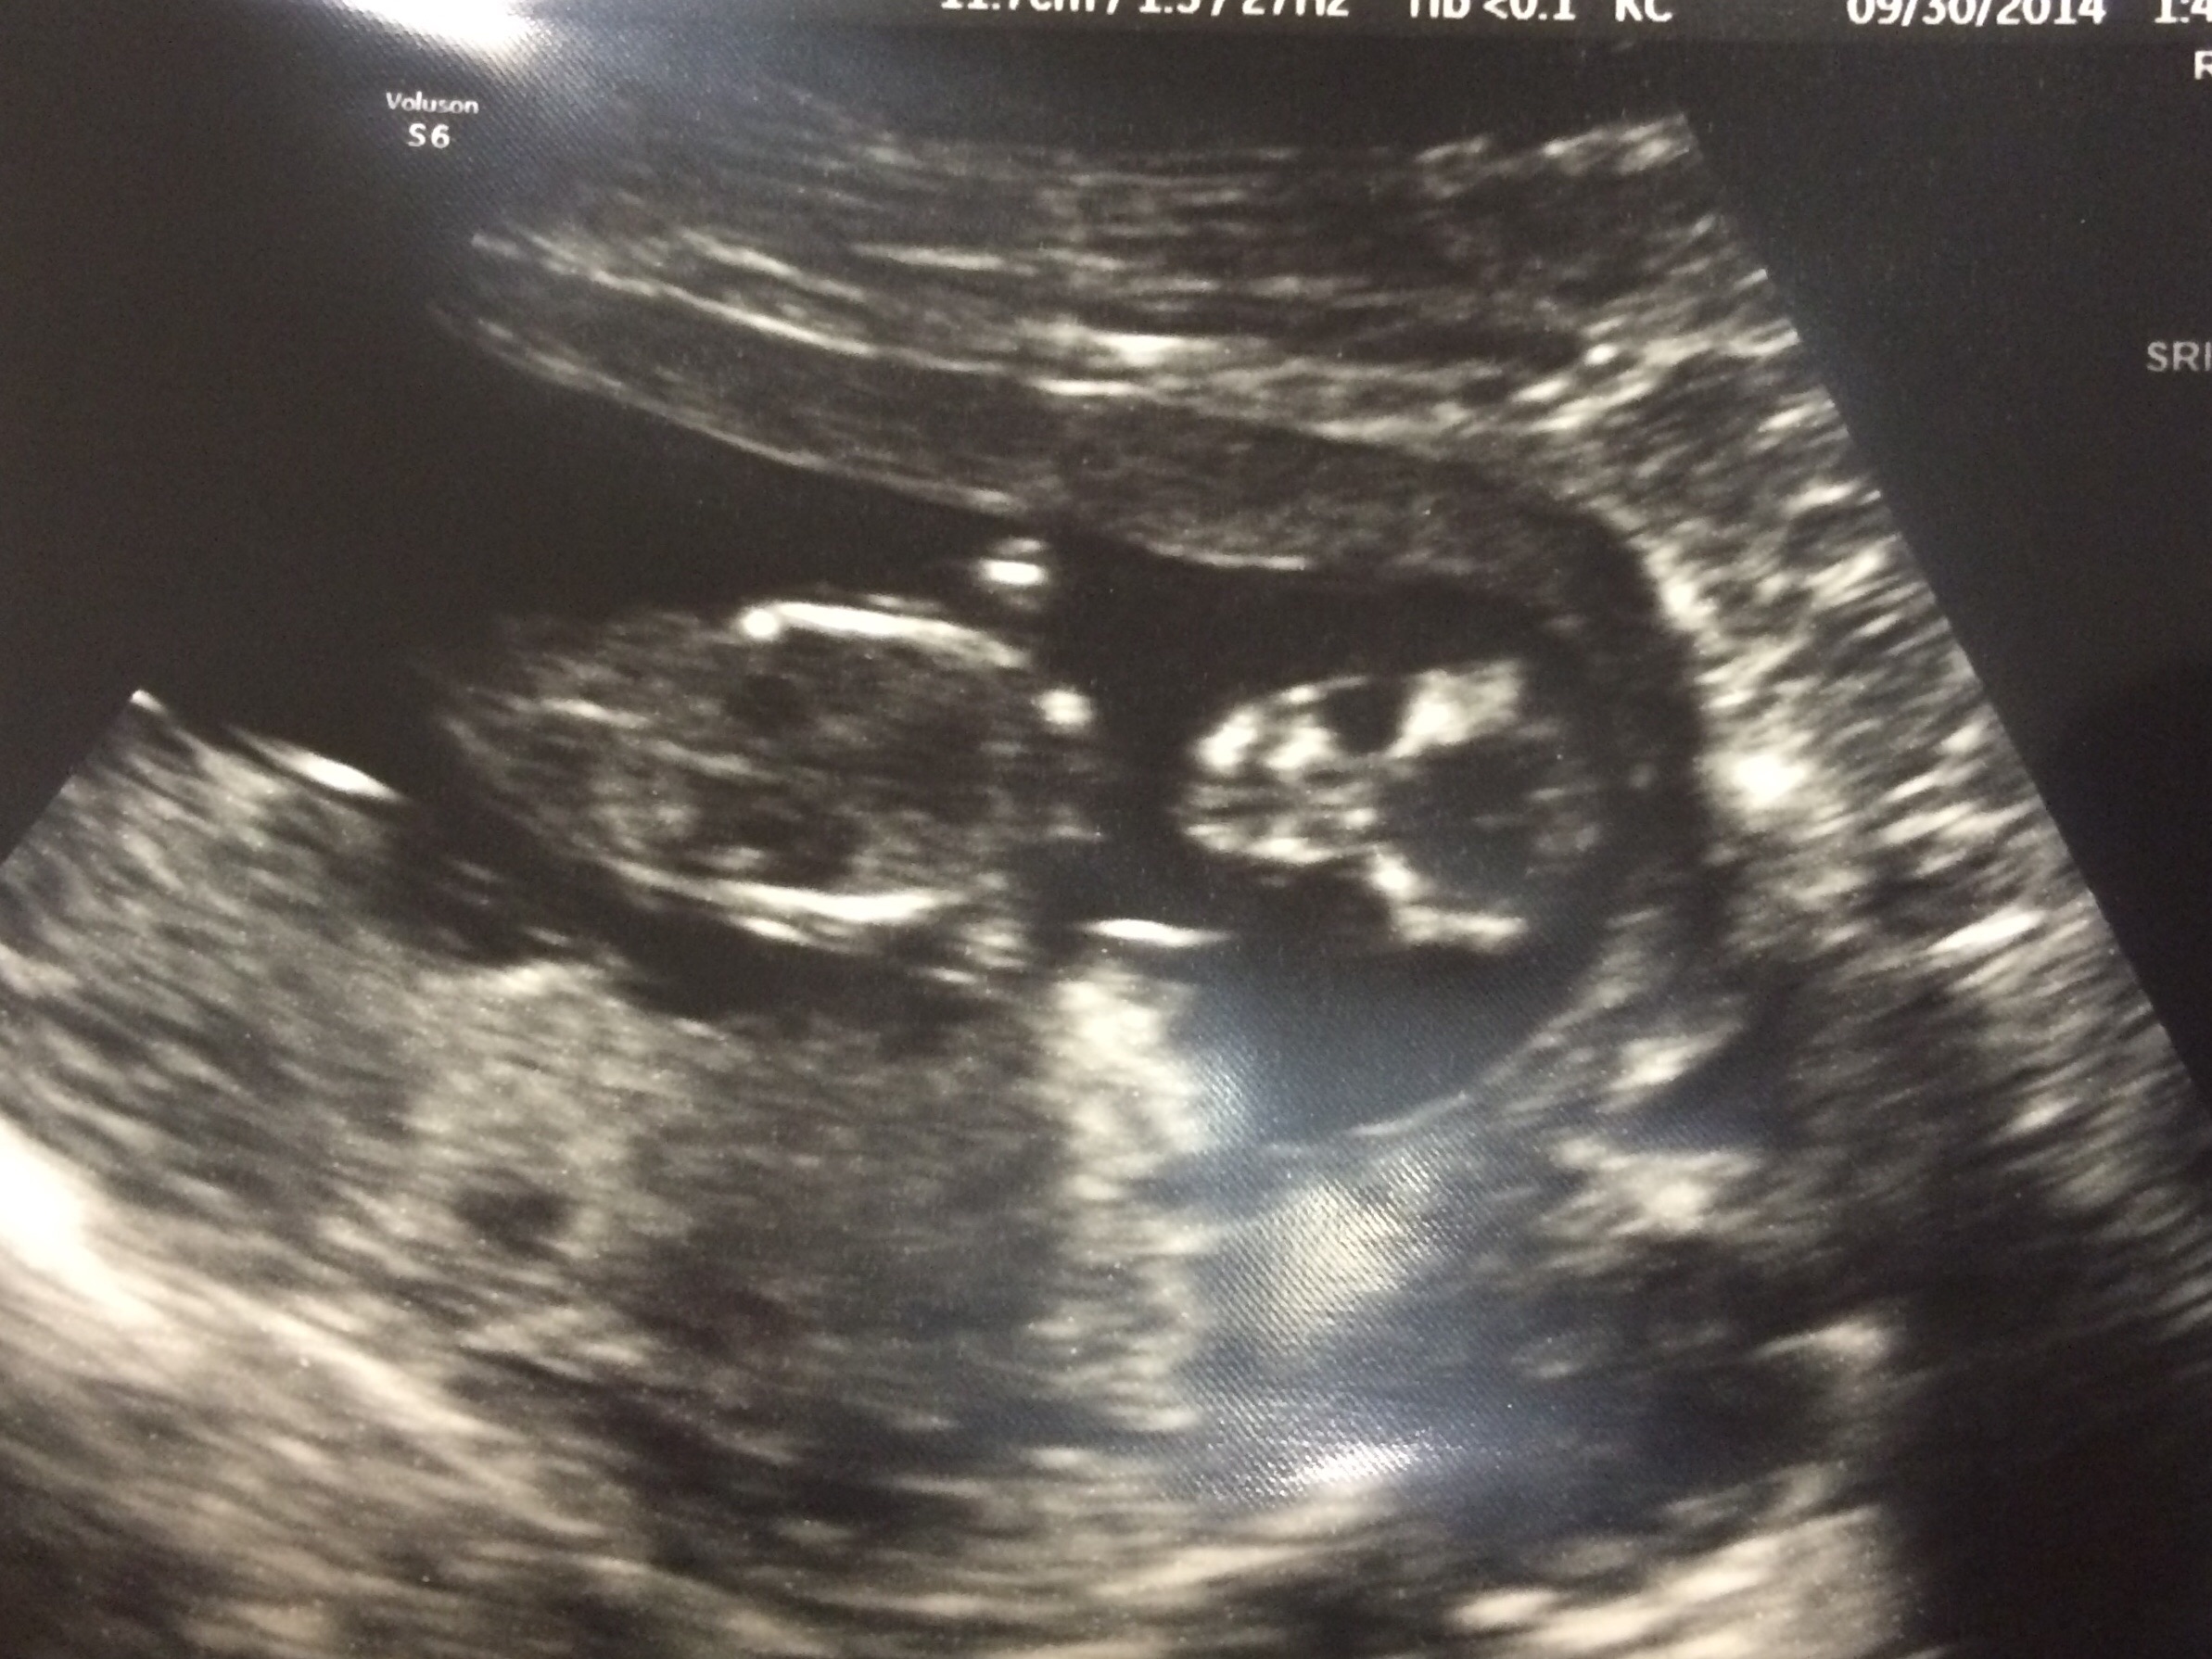

12 weeks 5 days HB 161

Asked the ultrasound tech if she had to guess the sex and she said girl which makes me very excited!!